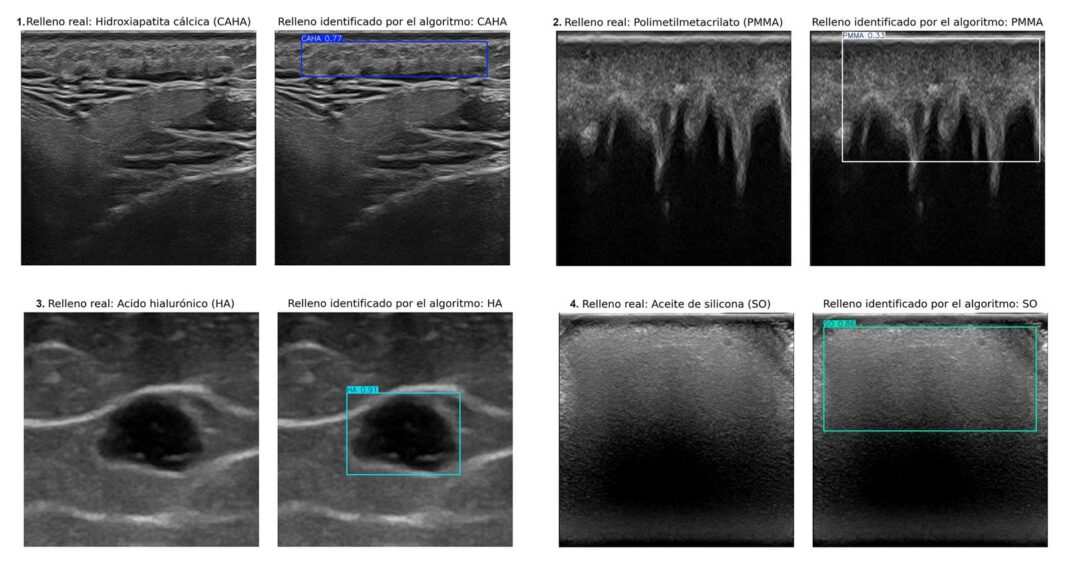

Un equipo internacional de investigadores de la Universidad de Granada (UGR) y la Universidad de Chile ha creado un sistema de inteligencia artificial que identifica automáticamente cuatro tipos de rellenos estéticos en imágenes ecográficas. El estudio, recientemente publicado en la revista Journal of Ultrasound in Medicine, promete agilizar el diagnóstico de complicaciones derivadas de estos tratamientos, mejorar la planificación clínica y facilitar una atención más eficaz incluso en centros con menos especialistas cualificados.

El nuevo algoritmo, basado en técnicas de aprendizaje profundo, ha sido desarrollado bajo la dirección de la doctora Ximena Worstman, de la Universidad de Chile, con la participación de Manuel Lozano y Francisco J. Rodríguez, del Departamento de Ciencias de la Computación e Inteligencia Artificial de la UGR. El sistema puede discriminar entre hidroxiapatita cálcica, ácido hialurónico, polimetilmetacrilato y aceite de silicona, cuatro de los rellenos más habituales.